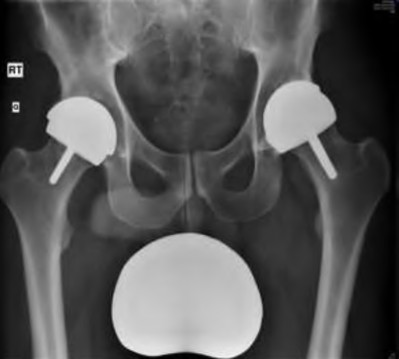

A dual mobility cup is often used in revision THA to reduce the risk of dislocation. Which of the following best describes the primary biomechanical principle of a dual mobility construct?

Explanation